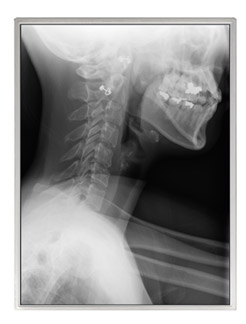

NEC液晶テクノロジー(代表取締役社長:奥野 和雄、本社:神奈川県川崎市)はこのたび、X線画像の読影診断をはじめとする医療用途向けに、UXGA(1600×1200ドット)表示対応、対角54cm(21.3型)アモルファスシリコンTFT(薄膜トランジスタ)モノクロ液晶ディスプレイモジュール「NL160120AM27-13A」を製品化し、本日から販売活動を開始します。

高透過率を実現する当社独自のSA-SFT技術と直下型高出力バックライトシステムとの組み合わせにより、UXGA以上の高解像度液晶ディスプレイモジュールとしては業界最高、かつシャウカステン(注)上でのX線フィルム読影時を凌ぐ1700cd/㎡の高輝度を実現。通常使用時には輝度を絞って使用することで、長期間安定した輝度を保つことも可能。 - コントラスト特性の改善